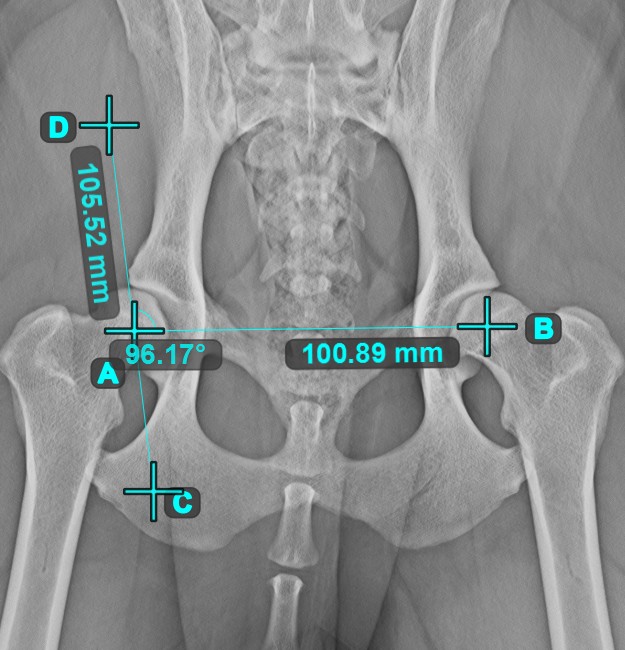

Angle of Lines¶

Select the tool from the left toolbar and assign it to one of the available mouse buttons. Start by selecting the first line from the ones already drawn on the scene, or place the start and end points to create the line. Follow the same steps for the second line of the measurement. The angle between the two lines will be automatically calculated.

Modify the start and end points of both lines by using the Select/Move Item tool. The angle between the two lines will be automatically recalculated.

If two lines do not intersect directly, the angle of their extended projections on the scene will be calculated.